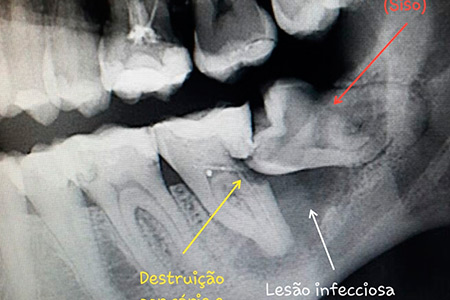

Dentre estes procedimentos podemos destacar: exodontia de terceiros molares (dentes do siso), cirurgias para remoção de pequenas lesões, cirurgias pré-protéticas, entre outras. As Cirurgias Orais são muitas vezes a solução para um bom resultado.